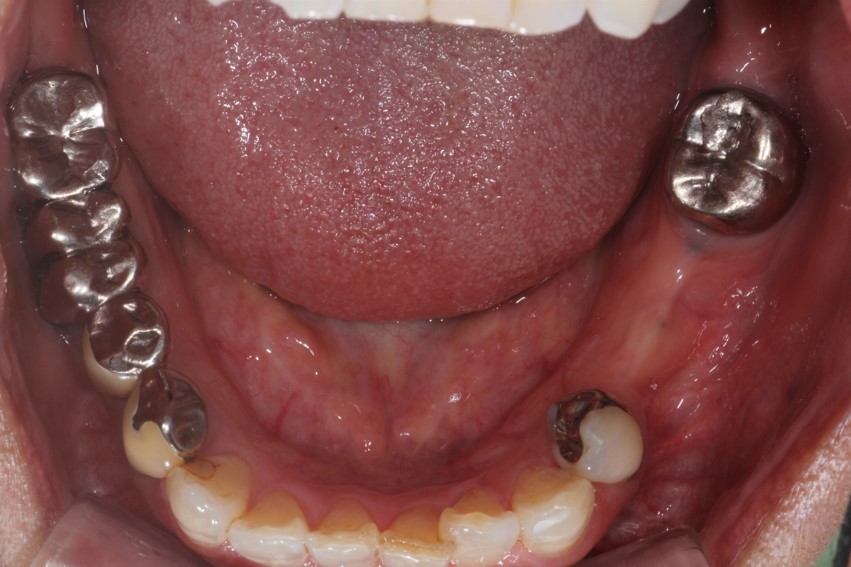

事例2

様々な入れ歯を製作してみました。

可能な限りうすく、違和感を軽減できるか色々な要素が関係してきます。

写真では解りにくいですが、お口に中に装着した際、入れ歯を入れているのが極力目立たないようにとも設計しています。